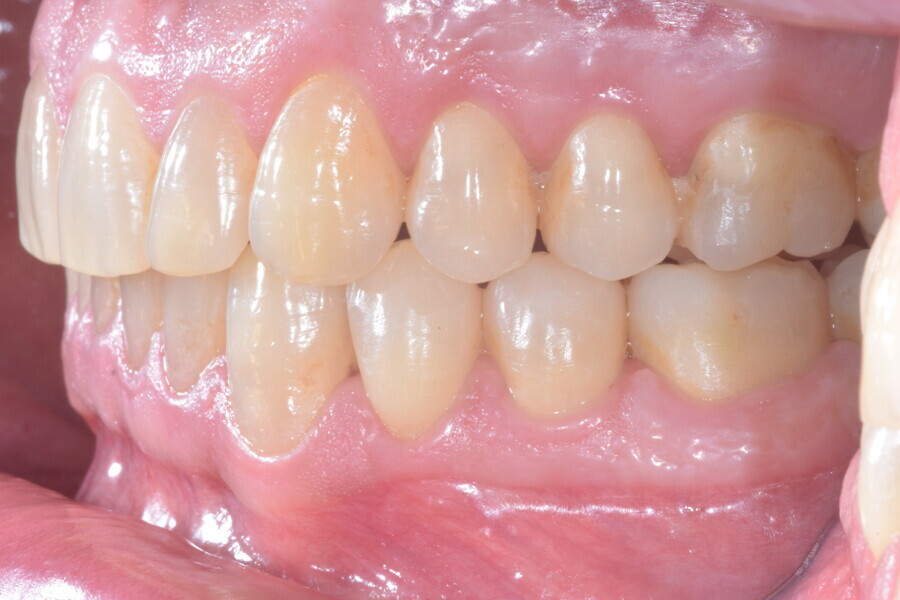

En raison de l’âge du patient, les aligneurs ont été changés tous les dix jours, dans le cadre d’un traitement d’une durée inférieure à six mois. À la fin de la première série d’aligneurs, un nouveau plan de traitement numérique comportant cinq autres aligneurs a été conçu, en vue d’améliorer l’intercuspidation des molaires sans élastiques. (Photos : Dr Alessandro Greco)

Le plan de traitement numérique (ClinCheck) avait prévu douze aligneurs pour l’arcade maxillaire et dix-sept pour l’arcade mandibulaire. Les objectifs du traitement visaient à combiner les mouvements verticaux d’extrusion des dents postérieures et les mouvements d’intrusion des dents antérieurs, au moyen de rampes d’occlusion, tout en utilisant des taquets d’extrusion pour assurer la désocclusion des dents postérieures et l’intrusion des dents antérieures inférieures, nécessaires au nivellement de l’arcade mandibulaire. La courbe de Spee a été nivelée et le profil plat ainsi que la position des lèvres ont été améliorés par une vestibulo-version des incisives supérieures et inférieures. Le plan avait prévu des élastiques de classe II pour faciliter la vestibulo-version des dents inférieures et les puissants contacts occlusaux postérieurs, avec une extrusion relative des dents postérieures. Une morphologie plus large de l’arcade et une intercuspidation idéale ont été obtenues par des mouvements de torque proches de 0° des dents latérales et postérieures supérieures. Aucune conception technique excessive n’avait été prévue dans le plan de traitement numérique. En raison de l’âge du patient, les aligneurs ont été changés tous les dix jours, dans le cadre d’un traitement d’une durée inférieure à six mois. À la fin de la première série d’aligneurs (Figs. 20–24), un nouveau plan de traitement numérique comportant cinq autres aligneurs a été conçu, en vue d’améliorer l’intercuspidation des molaires sans élastiques. La durée totale du traitement a donc été prolongée jusqu’à 7,5 mois puisque les aligneurs supplémentaires étaient changés toutes les semaines.

À la fin du traitement, on pouvait observer une relation de classe I des canines et des molaires, une légère augmentation de l’inclinaison des incisives supérieures (Ui-FH = 112°), une correction complète de l’inclinaison des incisives inférieures (IMPA = 97,09°) grâce à la vestibulo-version, et une légère amélioration de l’hypodivergence (SN-GoGn = 27°) résultant de l’extrusion relative des dents postérieures, et de l’utilisation d’élastiques de classe II — petite variation (1°) très intéressante compte tenu de l’âge du patient (Figs. 25–35). La ligne du sourire était harmonieuse et correspondait à une relation idéale entre les incisives supérieures et la lèvre inférieure. Le sourire avait été élargi grâce au contrôle du torque des segments latéraux et postérieurs.